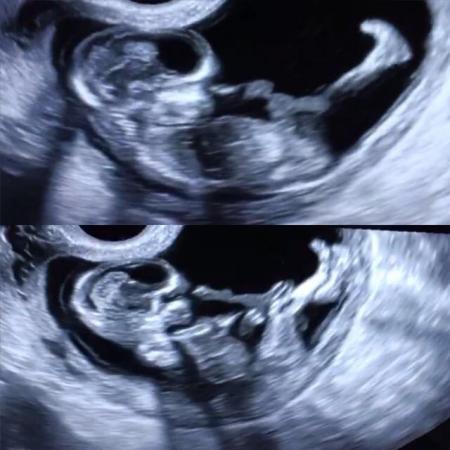

Hallo Ihr Lieben, ich melde mich hiermit zurück. Die kritische Zeit ist Gott sei Dank um und ich konnte meine Ängste etwas zurückfahren. Allerdings habe ich mich zwischenzeitlich von meinem Freund getrennt und bin damit Alleinerziehende. Gott sei dank haben wir uns im Guten getrennt und er möchte sich natürlich auch um unser Kind kümmern Aus unserem Haus müssen wir jetzt aber ausziehen.. also steht mir jetzt wieder Wohnungssuche und Umzug bevor. Manno Mir und meinen Krümmelchen geht es gut. Wir bekommen wohl einen Buben Morgen habe ich wieder einen Termin. Anbei ein Bildchen von der Fetometrie.

Bild zu Ich bin zurück. - Forum für August - Mamis

Huhu, Schön, dass du wieder da bist und die Sorgen nachgelassen haben. Tolles Bildchen. Liebe Grüße Brita